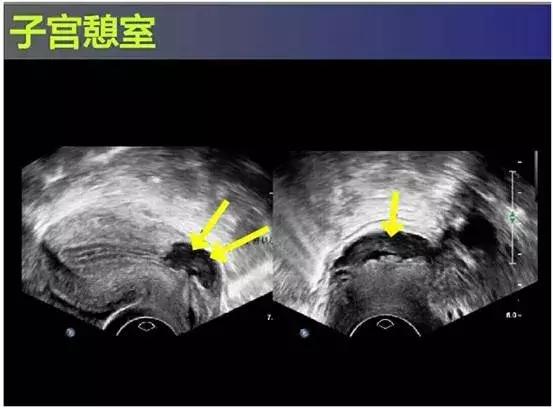

3. B超检查

子宫前壁下段存在宫腔内凸向浆膜层的锲形缺损,对缺损区进一步观察显示存在积雪,同时边界模糊,内部透声性较差,并且回声区肌层较薄,宫腔内膜线中断。